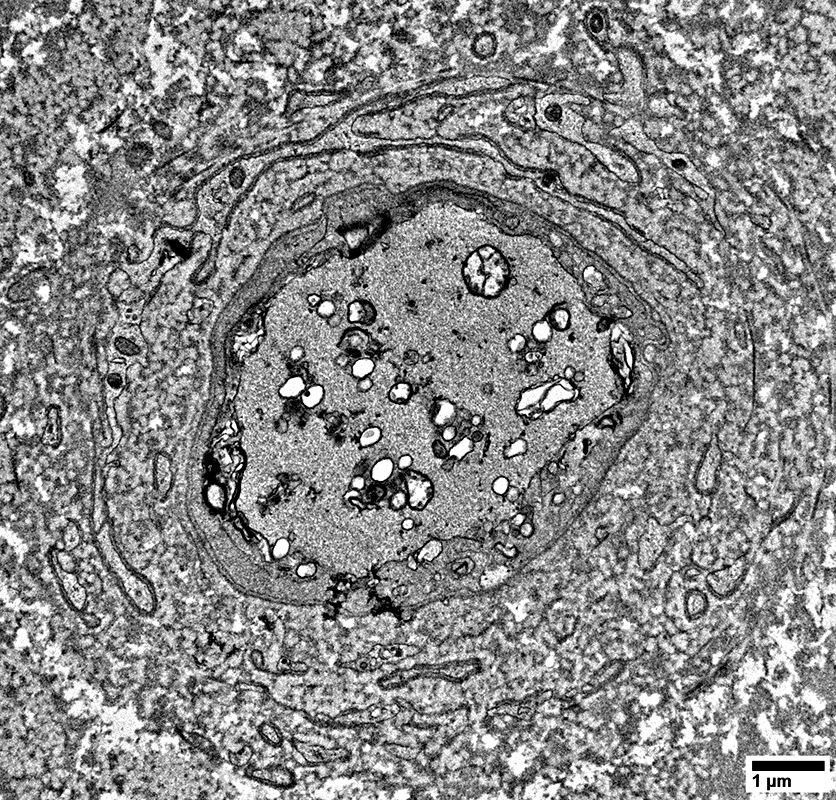

Non-Myelinating Schwann Cells & Unmyelinated Small Axons

Unmyelinated Axons

Numbers: Relatively preserved; Several per Schwann cell

Non-myeliinating Schwann cells

May have pale cytoplasm (Below)

From: R Schmidt